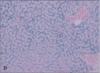

bone marrow core biopsy (5 year old)

33

bone marrow core biopsy (35 years old)

34

bone marrow core biopsy

top circle: erythroid

bottom circle: myeloid

arrow: megakaryoctye

35

normal bone marrow